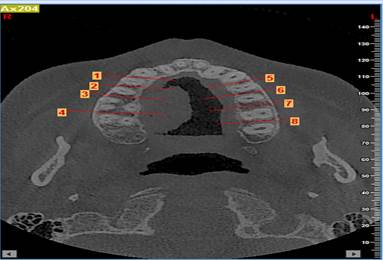

§ Se realizaron diferentes cortes coronales entre cada pieza dental de la zona molar del maxilar (imagen 3)

§ Por cada corte se tomaba en cuenta 0.5 mm desde la cresta alveolar hacia la zona de la línea mucogingival. (imagen 1)

§ Con una profundidad de 0.6 mm a través de la cortical hacia la tabla ósea que es el valor mínimo de un microtornillo ortodóntico en sentido horizontal (imagen 2) interradicular. Las Zonas a medir fueron:

o Z_4_D que corresponde al espacio entre las piezas 1.3 – 1.4 (Zona 4 Derecha)

o Z_5_D que corresponde al espacio entre las piezas 1.4 – 1.5 (Zona 5 Derecha)

o Z_6_D que corresponde al espacio entre las piezas 1.5 – 1.6 (Zona 6 Derecha)

o Z_7_D que corresponde al espacio entre las piezas 1.6 – 1.7 (Zona 7 Derecha)

o Z_4_I que corresponde al espacio entre las piezas 2.3 – 2.4 (Zona 4 Izquierda)

o Z_5_I que corresponde al espacio entre las piezas 2.4 – 2.5 (Zona 5 Izquierda)

o Z_6_I que corresponde al espacio entre las piezas 2.5 – 2.6 (Zona 6 Izquierda)

o Z_7_I que corresponde al espacio entre las piezas 2.6 – 2.7(Zona 7 Izquierda)

Finalmente se mide las Unidades Hounsfield (UH) a 6 mm intraóseo e interradicular. (Imagen 1,2,3,4).